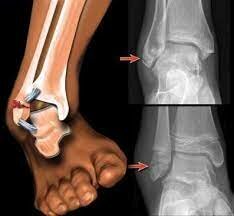

Agudas: Tienen un inicio repentino (traumático o no traumático) provocado por una caída,

un choque con otro deportista o con un objeto, un mal gesto técnico o una carga

que supere los límites fisiológicos